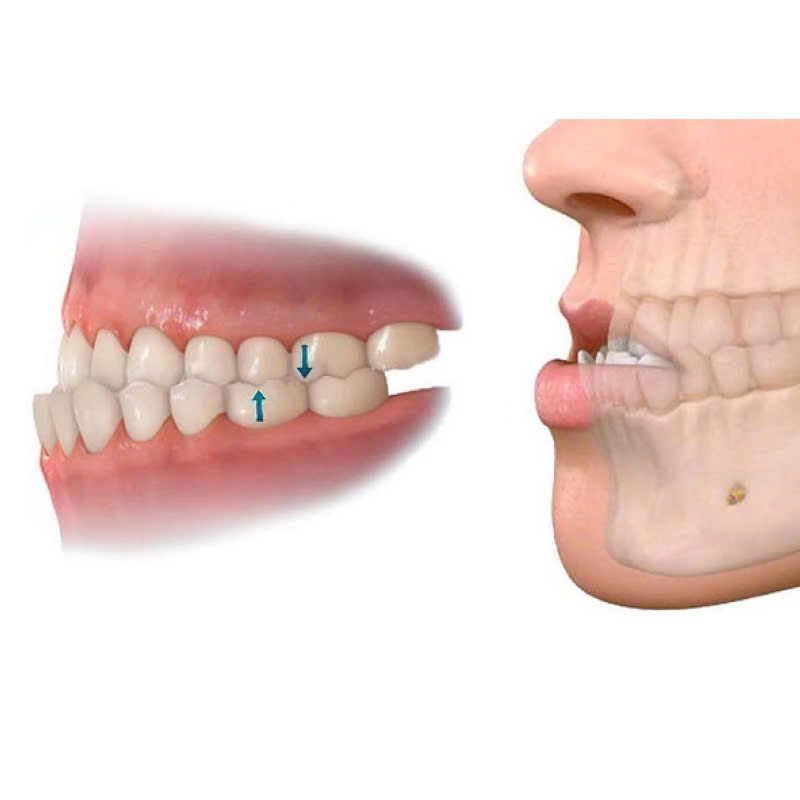

Chỉnh hàm dưới là một dịch vụ nha khoa chuyên biệt nhằm khắc phục tình trạng lệch lạc, bất thường về cấu trúc hàm dưới, mang lại cho bạn một hàm răng đều đẹp và có nụ cười tự tin rạng rỡ. Hàm dưới lệch lạc có thể do nhiều yếu tố gây ra, như: Bẩm sinh: Di truyền từ bố mẹ, do dị tật bẩm sinh về xương hàm dưới. Sau chấn thương: Do tai nạn, tác động mạnh vào vùng hàm mặt. Bệnh lý răng miệng: Răng mọc chen chúc, sai lệch, thiếu răng. Thói quen xấu: Ngậm miệng, nghiến răng.

- Những người có hàm dưới lệch lạc, gây mất thẩm mỹ và ảnh hưởng đến chức năng ăn nhai: Chỉnh hàm dưới sẽ giúp khắc phục tình trạng này, mang lại một nụ cười rạng rỡ và khuôn mặt cân đối.

- Những người có cấu trúc xương hàm dưới bất thường: Chỉnh hàm dưới là giải pháp hiệu quả để sửa chữa các dị tật về xương hàm dưới.